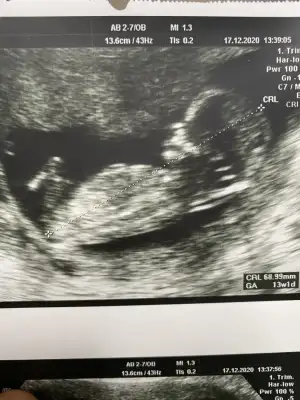

canım senin attıgın usg de bebegi yandan görüyoruz ya ben kız gibi hissettim inan icimden öyle geldi kendi usg görüntülerime baktım video dan hep bir cıkıntı var bana erkek dendi 12. hafta dan beri sana erkege benziyor derken bacaklarının arasını gösterdi mi dr şuan pc den yazıyorum telden girip 14. hafta daki usg bacaklarının arasını atıcam hala senin kızın olucak gibi geliyor bana hayırlısı ama öyle geliyor ne yapayım :)

Yok canım benim oranda vermedi pipi de göstermedi ondan kafam karıstı yan yatiyo dedi görünen şey kordonda olabilir pipi de 16. Haftada tam belli olur dedi ben yüzde birlik ihtimalde olsa soylemeliyim dedi ondan kafam karıstı

Oran da vermeyince yani bildiğin diğer erkek gibi dediyse değiebilir o benim usg görünce kız doğdu içime

usg gören herkes kıza benziyor yandan dedi ama bilemiyorum